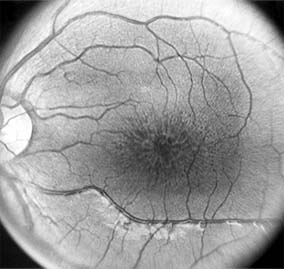

Cone-Rod Dystrophies

The cone-rod dystrophies constitute a relatively rare group of disorders that may be regarded as a single entity showing variable expressivity. Most cases are sporadic, but familial cases are usually transmitted by an autosomal dominant inheritance pattern. Cone-rod dystrophy is characterized by predominant involvement of the cone photoreceptors with progressive color vision defects and associated loss of visual acuity. A bilateral and symmetric bulls-eye pattern of depigmentation and a corresponding zone of hyperfluorescence surrounding a central nonfluorescent spot (similar to that seen in chloroquine retinopathy) are the most commonly described biomicroscopic and angiographic changes in these patients (Figure 10-15). As the disease progresses, the electroretinogram shows marked loss of cone function associated with a slight to moderate loss of rod function. Histopathologic study shows absence of macular and paramacular photoreceptors, and there is associated pigment epithelium degeneration.

Figure 10-15

Figure 10-15: Cone dystrophy with depigmentation and a bull's-eye pattern to the macula.